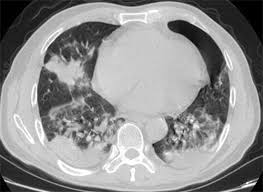

Lung Cancer Pictures Ct Scan X Ray And More from post.healthline.com The general prognosis of lung cancer is poor because doctors tend not to find the disease until it is at an advanced stage. When helen began coughing up phlegm in january she thought she just had a chest infection. Lung pathology of fatal severe acute respiratory syndrome. Lung cancer forms in the tissues of the lungs, most often in the cells that line air passages. Lung tumors can block the airway, causing frequent infections such as chest pain: An infection or abscess is perhaps the most common cause behind a mass that is mistaken for a tumor. An ache or pain when breathing or coughing. Although people who have persistent chest infections.